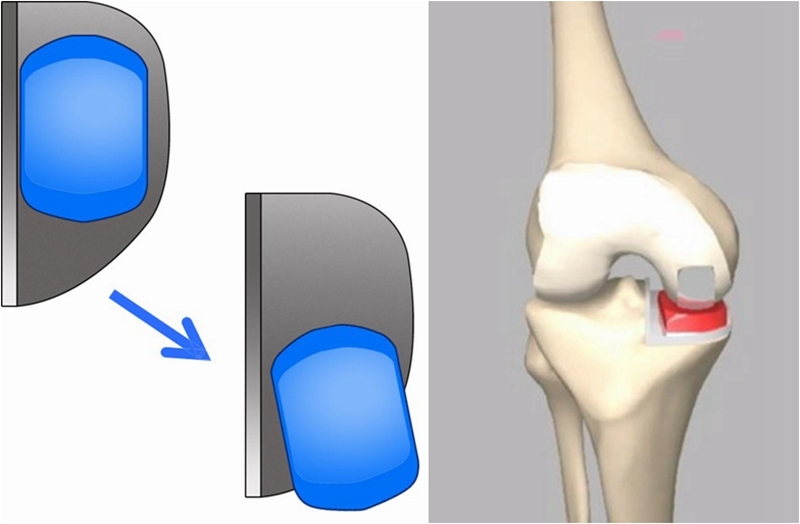

OUKA原理:充分填充,恢复自然。

伸直位外翻应力下内侧间隙打开

屈曲90°位外翻应力下内侧间隙打开

垫片移动轨迹测量